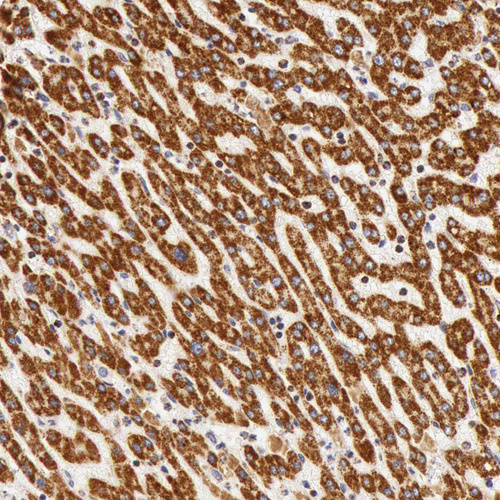

Immunohistochemical staining of human kidney, liver, prostate and small intestine using Anti-ATP5B antibody HPA001520 (A) shows similar protein distribution across tissues to independent antibody HPA001528 (B).